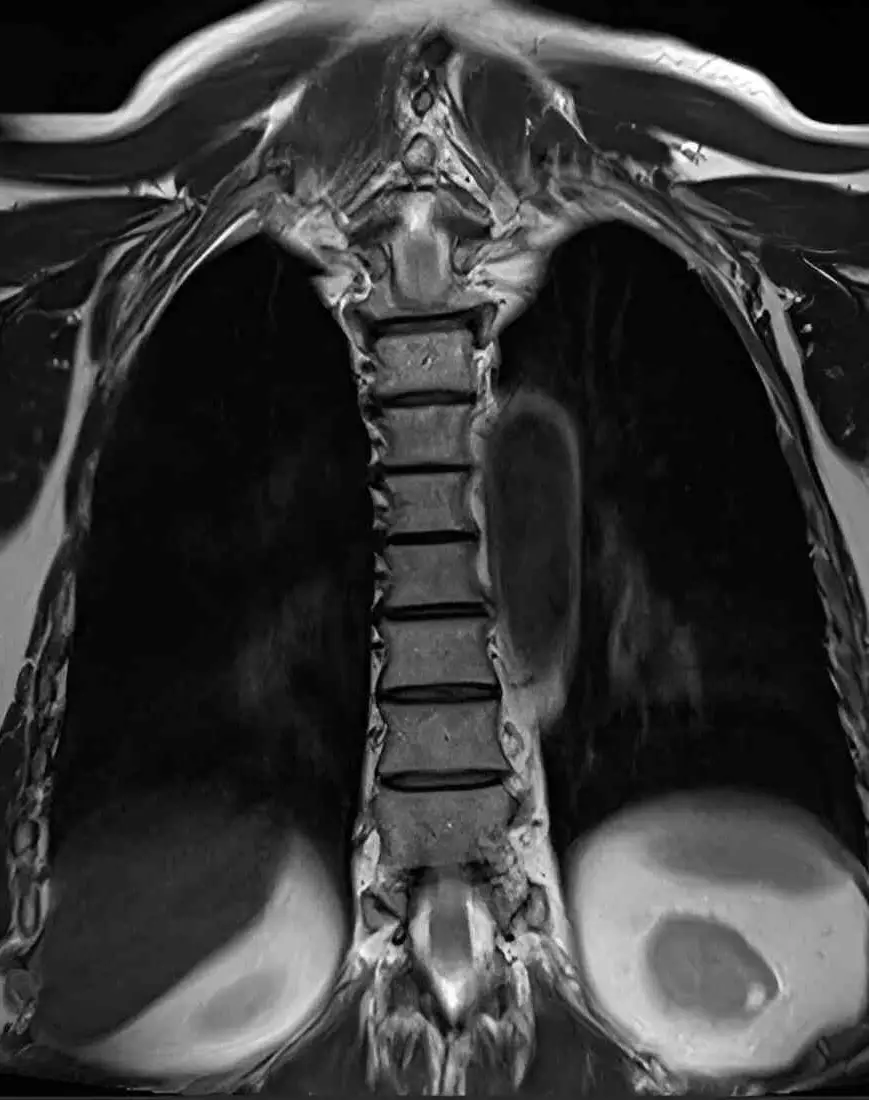

МРТ грудного отдела позвоночника

Визуализация позвонков, межпозвонковых дисков, спинного мозга, спинномозговых корешков, окружающих мягких тканей.